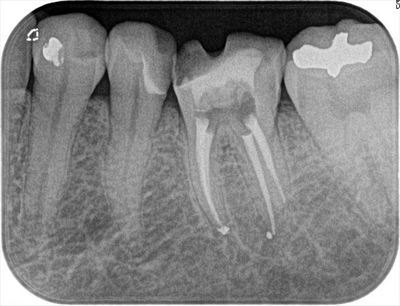

内部がドロドロになっていた左下第一大臼歯の根管充填を行いました。2017.12.16

下記のブログ記事に書きました左下第一大臼歯の根管充填を本日ついに行いました。(レントゲン画像中央)

根管充填後のデンタルレントゲン写真です。

4根管をそれぞれ根管充填しています。